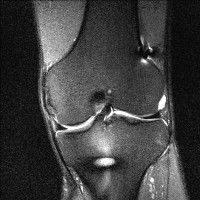

무릎 mri 간단히 봐주실 수 있으시나요 ㅠㅠ

안녕하세요 8년전 십자인대 수술하고 최근 무리한 운동에 무릎 불편감이 생겨서

mri 찍었습니다.

진단결과는 첫 찍은 병원에서 활액막염 이라는 진단을 받았습니다. 혹시 봐주실 수 있으실까요?

올라온 MRI가 단편적이라서 정확한 진단에 어려움이 있지만 십자인대에는 큰 이상이 있지는 않은것 같으며, 무릎관절내 물이 있는 것으로 보아 활액막염의 진단이 맞을 것 같습니다.

하지만 단편적인 영상이기 때문에 촬영병원에서 정확한 판독지 등을 받으시는 것이 좋겠습니다.